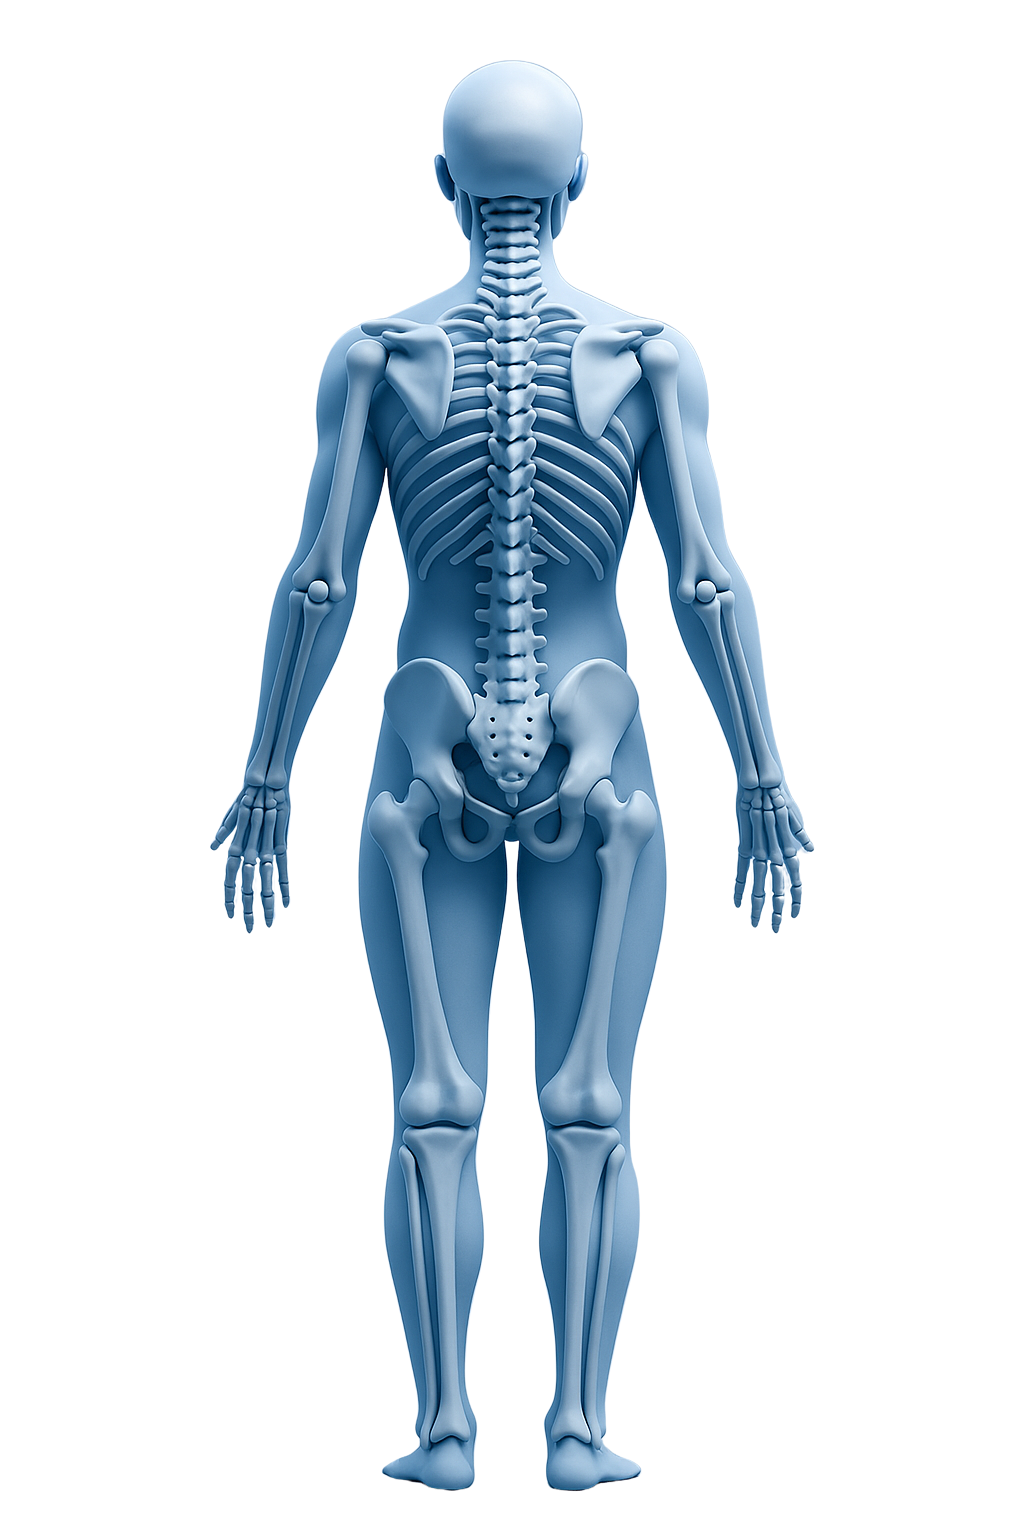

Step into the future of orthopedic care with our Interactive Explorer a smart, visual experience that lets you discover how advanced technology and precision surgery restore movement and relieve pain. Explore each joint, learn about modern treatments, and see how Dr Attaallh Alrefaee’s expertise helps patients move confidently again.

Knee Treatments

ACL tears, meniscus injuries, arthritis discover minimally invasive arthroscopy and robotic joint replacement for faster, safer recovery.

Shoulder Treatments

From rotator cuff tears to dislocations, advanced arthroscopic surgery restores mobility and strength.

Hip & Joint Replacement

Robotic precision and 3D implants ensure natural movement and long-term results.

Sports Injuries

Whether you’re an athlete or a weekend runner, personalized treatment gets you back in motion.